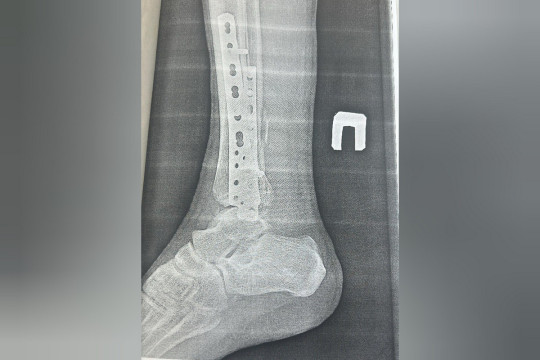

Фото: Минздрав Амурской области— Как правило, при ДТП пострадавший получает не одну травму, а множество: с повреждением нескольких сегментов конечностей, или в сочетании с повреждением внутренних органов. Потому наше отделение и называется отделением сочетанной травмы — поступают с переломами ребер, таза, с разрывом мочевого пузыря, с черепно-мозговыми травмами и так далее. И сопровождается это травматическим шоком. Такие пациенты доставляются к нам практически ежедневно, — рассказал заведующий травматологическим отделением (сочетанной травмы) АОКБ, являющегося травмацентром первого уровня, Игорь Бородин.

Как рассказал Игорь Сергеевич, иногда одному пациенту выполняется одновременно от одной до трех операций. В среднем они идут от получаса до двух.

— Наша областная больница — многопрофильная, — пояснил Игорь Бородин. — И когда пострадавших привозят в приемное отделение, с ними комплексно работает мультидисциплинарная бригада, в составе которой нейрохирург, травматолог, абдоминальный и торокальный хирурги, другие специалисты. Больного обследуют максимально – для этого в приемном отделении есть, практически, все медицинское оборудование.